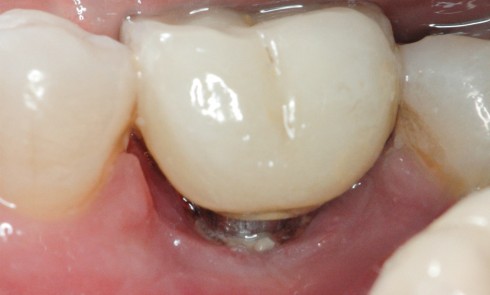

Le patient 70 ans Pas d’antécédents médicaux Ne fume pas Hygiène correcte L’implant Site 23 Mis en place il y...